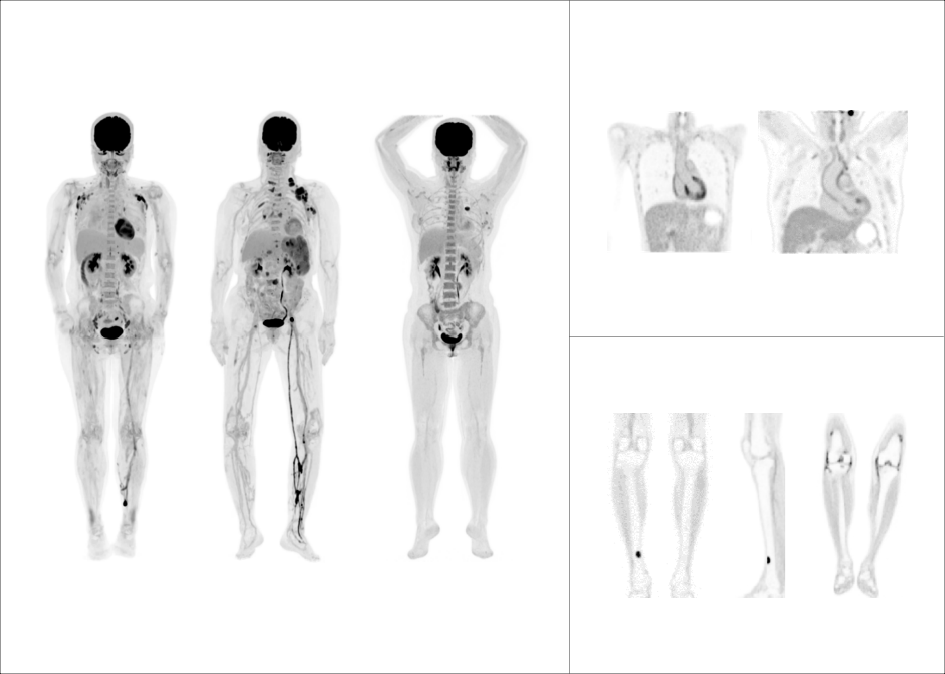

uMI Panorama搭载联影首款高端医学影像专用芯片,首次实现180ps量级超高时间分辨率,全维度性能业界领先,全力推动分子影像技术朝着更精准、更有温度以及诊疗一体化三大方向加速演进。

由精细向精准

全面刷新PET影像感官